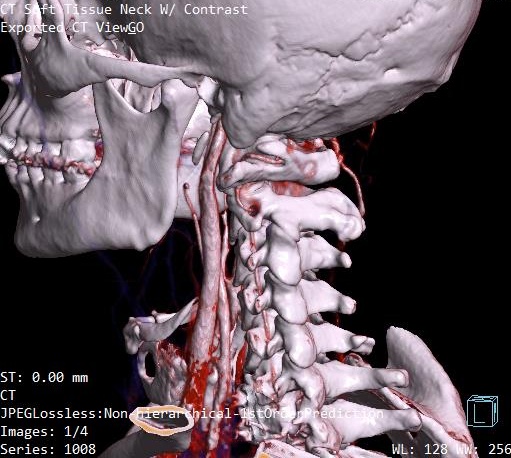

@jrhode2873 axial view is the best to see the IJV compression. If you go to the axial view, look for C1. I’ve attached my own imaging to help you find it. It’s the vertebrae that has wings!

It’s often hard to tell if the styloids are at play with IJV compression in the 3D models. Sometimes it just ends up being C1 causing the compression, but can never know for sure unless I see the axial view!

@jrhode2873 - Your right IJV is definitely compressed & it looks like it’s predominantly being caused by C1. The left also has some contact w/ C1 but doesn’t look like it’s got the serious compression that the right side has.

The greater hornse of your hyoid look somewhat long which means they could be making contact w/ your carotids in some head positions. Do your carotid arteries show up in your imaging or was this just a CTV? If you have any carotid pics & could give us some views of your hyoid bone w/ respect to the vascular tissues around it, that would be great.

You, like so many of our members have lost the lordotic curve in your cervical spine. That brings the styloids & potentially the greater horns of the hyoid closer to the nerves & blood vessels in the neck.